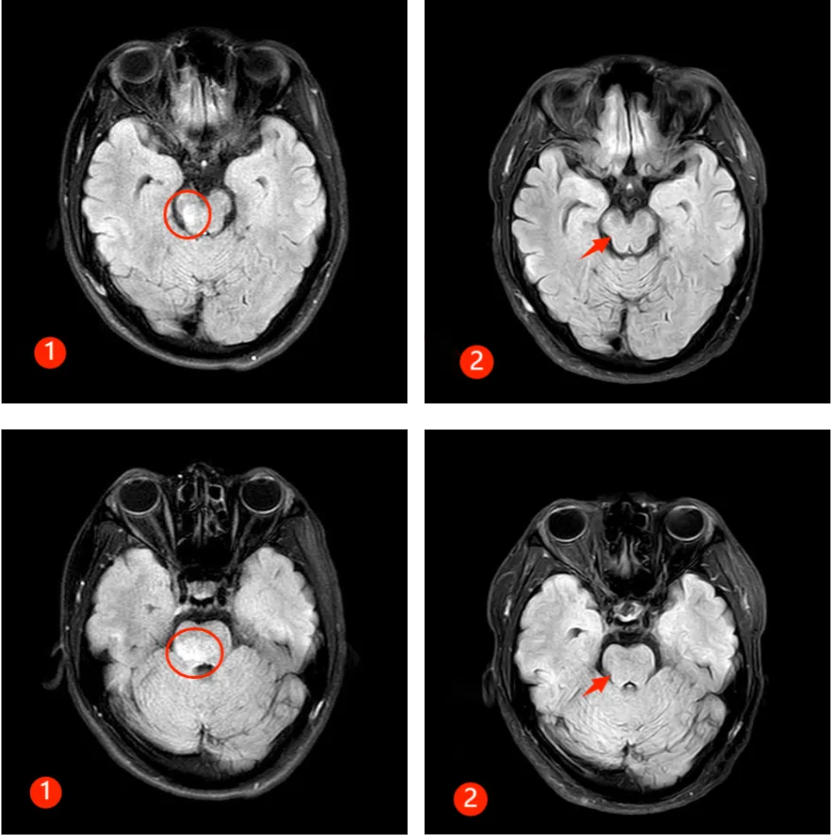

半年前,30 来岁的谭先生突然出现颈肩部疼痛不适及肢体麻木,此后短短数天迅速出现四肢瘫痪及大小便失禁,生活不能自理。正值风华正茂的年纪,谭先生一时无法接受,心急如焚的父母带着吓坏了的谭先生来郑州大学第五附属医院就诊,入住神经内科二病区。入科时患者已四肢全瘫,紧急完善相关检查,发现患者脑干、颈髓、胸髓、腰髓广泛病变(见图①),随后完善腰穿及相关抗体检查,最终确诊为 MOGAD。

经过及时的免疫治疗,患者病情逐渐好转,出院时患者已能下床行走,再次拾起对生活的信心,复查磁共振,患者脑干、颈髓、胸髓、腰髓的病变已明显好转(见下图②)。半年后随访,患者已恢复正常的生活,预后很好。